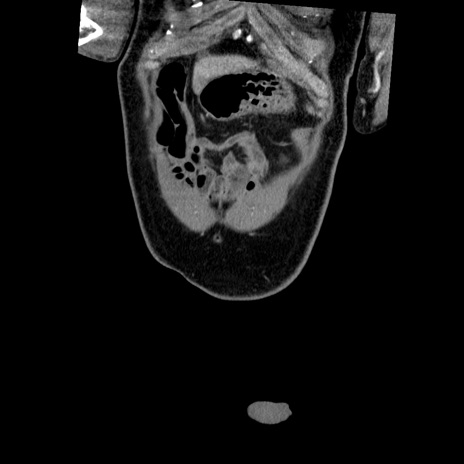

症例

横断像